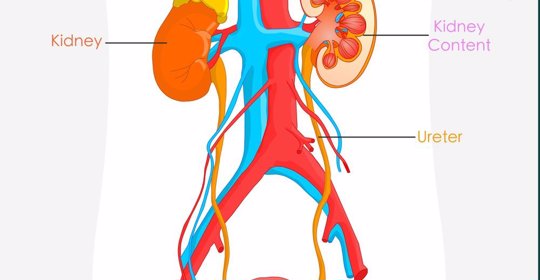

輸精管疼痛:男性生殖系統問題解析

陰囊腫脹:男性健康暢談,認知陰囊腫脹的原因與應對

射精疼:男性生殖問題分析與治療考慮

睪丸下垂:男性生殖器睪丸下垂的生理與可能病理原因!

精液裡有血絲:男性生殖系統的紅旗,認識精液裡有血絲的可能疾病關聯!

無睪丸:男性生殖健康詳解,診斷與治療全方位!

睪丸微小:男性健康預警,症狀及其背後的原因解析